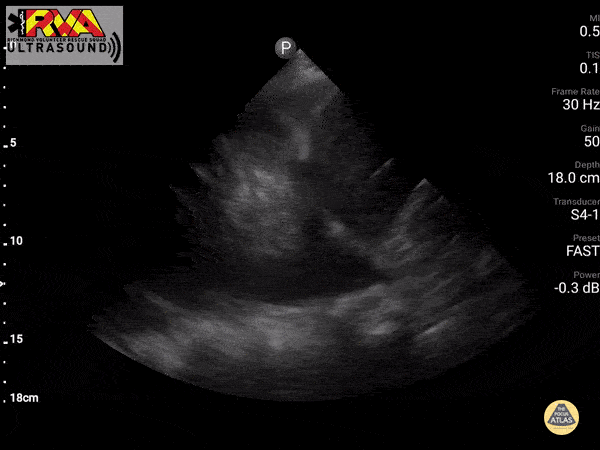

What is seen in this US?

B-lines

B-lines on thoracic ultrasound should be described as vertical, hyperechoic artifacts that arise from the pleural line, extend to the bottom of the screen without fading, and move synchronously with lung sliding. The presence of multiple B-lines (≥3 per intercostal space) is indicative of alveolar-interstitial syndrome